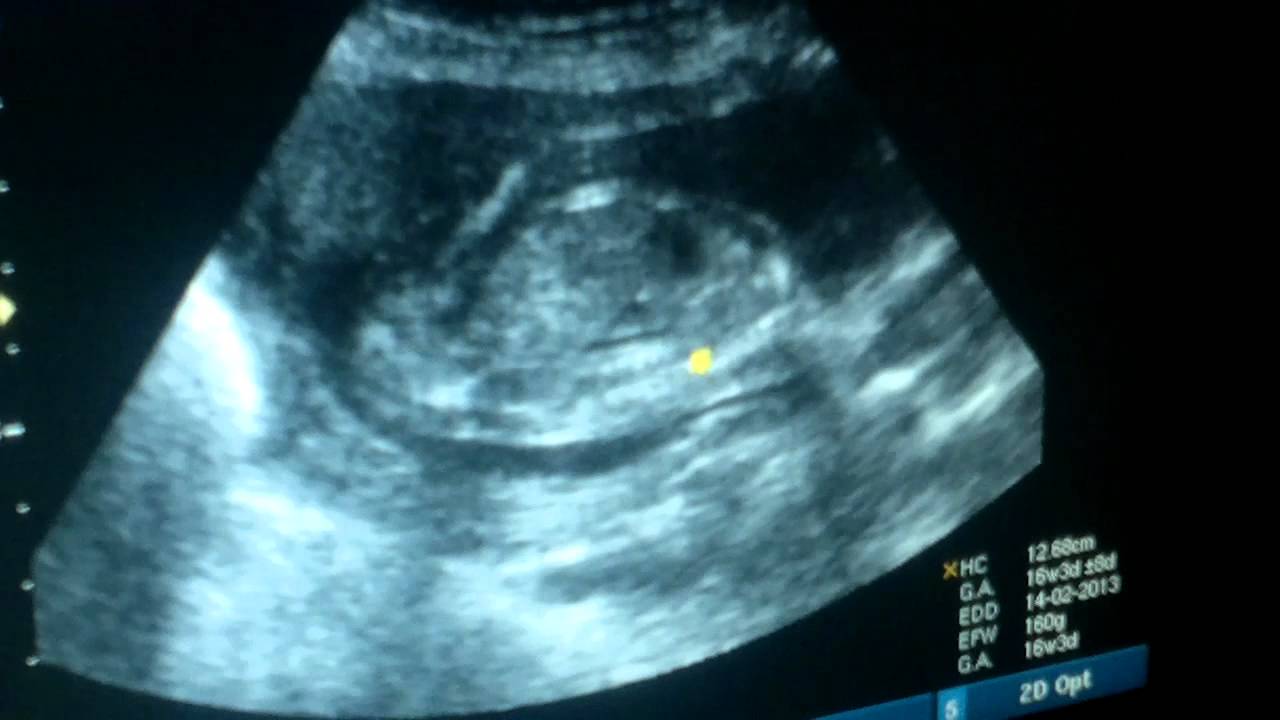

حصد فيديو لجنين يصفق داخل رحم أمه أكثر من مليوني مشاهدة على موقع يوتيوب.

وأثار الفيديو ضجة على مواقع التواصل الاجتماعي، إذ ظهر الجنين يصفق على أنغام الأغنية الإنجليزية "إذا كنت سعيدا صفق بيديك"، والتي كان والده يغنيها في إحدى جلسات التصوير بالأمواج فوق الصوتية.

ونقلت صحيفة مترو البريطانية، عن جين كاردينال والدة الطفل، قولها "إن الفيديو حقيقي، وإن طفلها صفق بالفعل، ولكن ليس على أنغام الأغنية".

وأضافت كاردينال "قام الطبيب بإعادة شريط التسجيل، وبدأ والده في الغناء بشكل متزامن مع تصفيقه، لنحصل على هذا الفيديو المدهش".